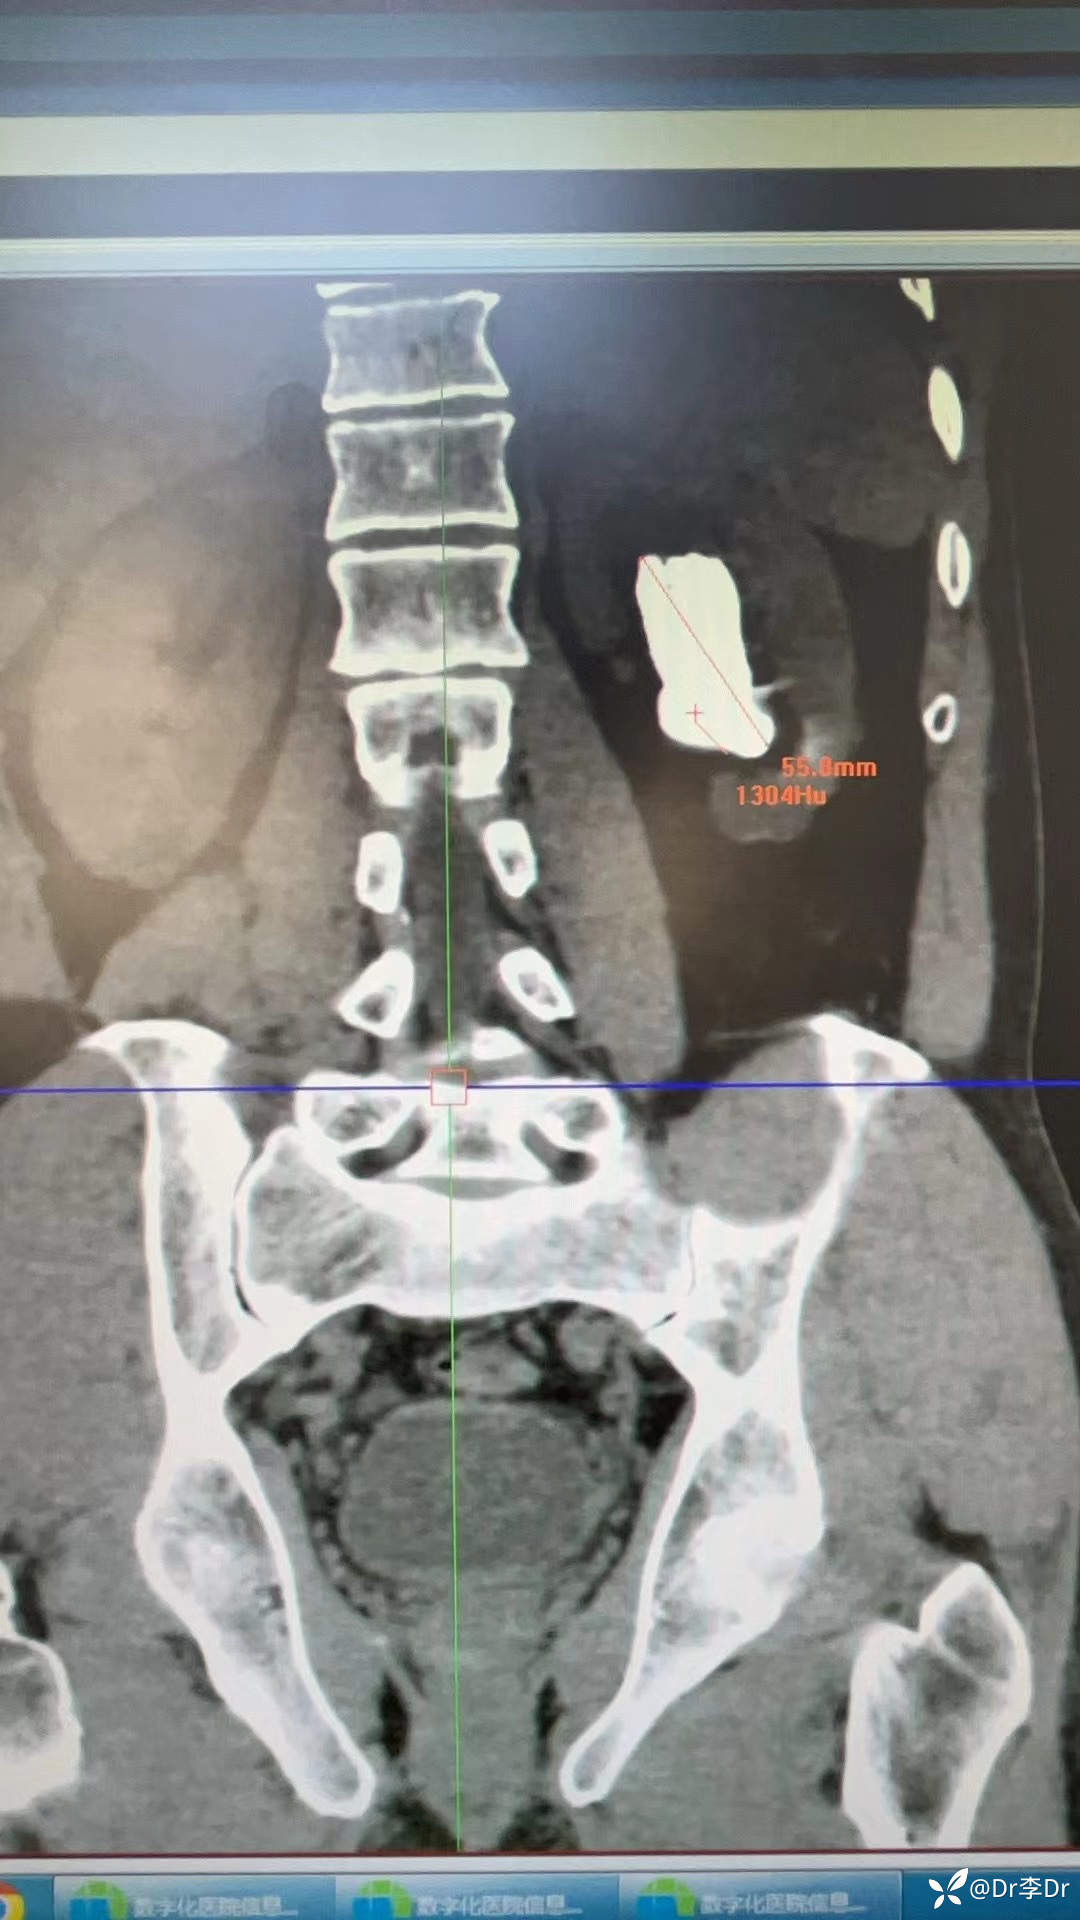

鹿角形结石你见过吗?这样的结石如何治疗?

现病史:患者2周前无明显诱因出现左侧腰腹部疼痛,行泌尿系超声示:1.双肾囊肿;2.左肾结石(多发);3前列腺增生伴钙化。今为进一步诊治,来我院,门诊以“左侧肾结石、前列腺增生、双侧单纯性肾囊肿”患者精神饮食睡眠尚可,大便正常。尿常规:白细胞(3+),硝酸盐(+),尿培养大肠埃希菌,耐药。